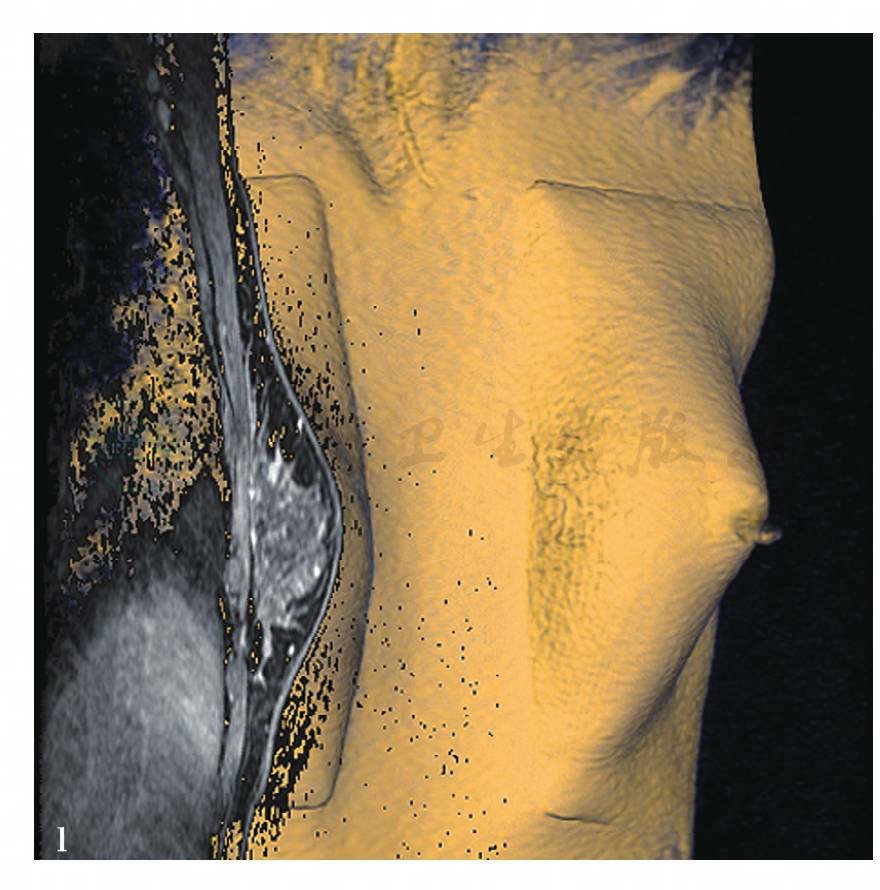

图20 l,MRI容积重建(VR)图